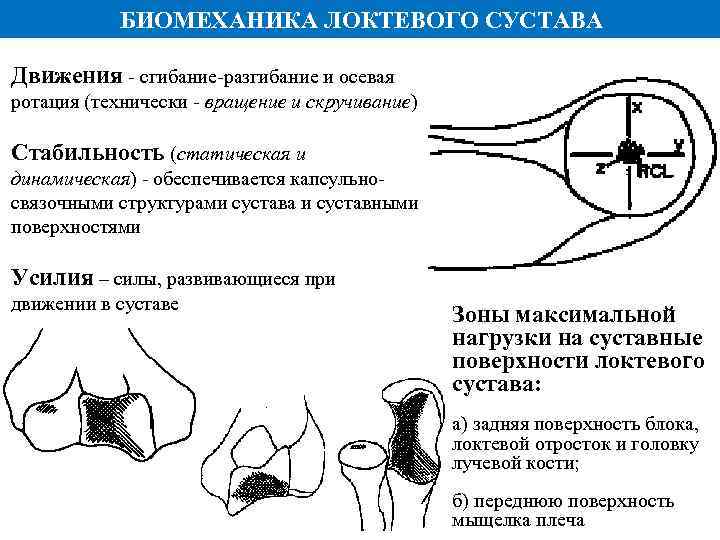

БИОМЕХАНИКА ЛОКТЕВОГО СУСТАВА Движения - сгибание-разгибание и осевая ротация (технически - вращение и скручивание) Стабильность (статическая и динамическая) - обеспечивается капсульносвязочными структурами сустава и суставными поверхностями Усилия – силы, развивающиеся при движении в суставе Зоны максимальной нагрузки на суставные поверхности локтевого сустава: а) задняя поверхность блока, локтевой отросток и головку лучевой кости; б) переднюю поверхность мыщелка плеча

БИОМЕХАНИКА ЛОКТЕВОГО СУСТАВА Движения - сгибание-разгибание и осевая ротация (технически - вращение и скручивание) Стабильность (статическая и динамическая) - обеспечивается капсульносвязочными структурами сустава и суставными поверхностями Усилия – силы, развивающиеся при движении в суставе Зоны максимальной нагрузки на суставные поверхности локтевого сустава: а) задняя поверхность блока, локтевой отросток и головку лучевой кости; б) переднюю поверхность мыщелка плеча